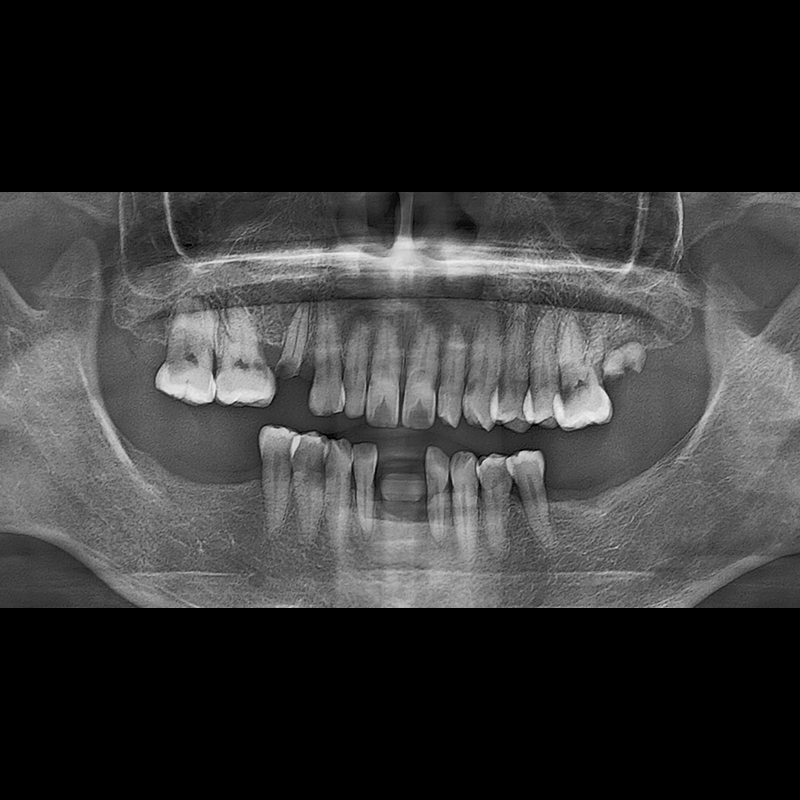

IMPLANT

BEFORE AFTER

Implant before and after 2025.05.30

Implants were placed in the missing tooth and in the tooth position where it was difficult to save.